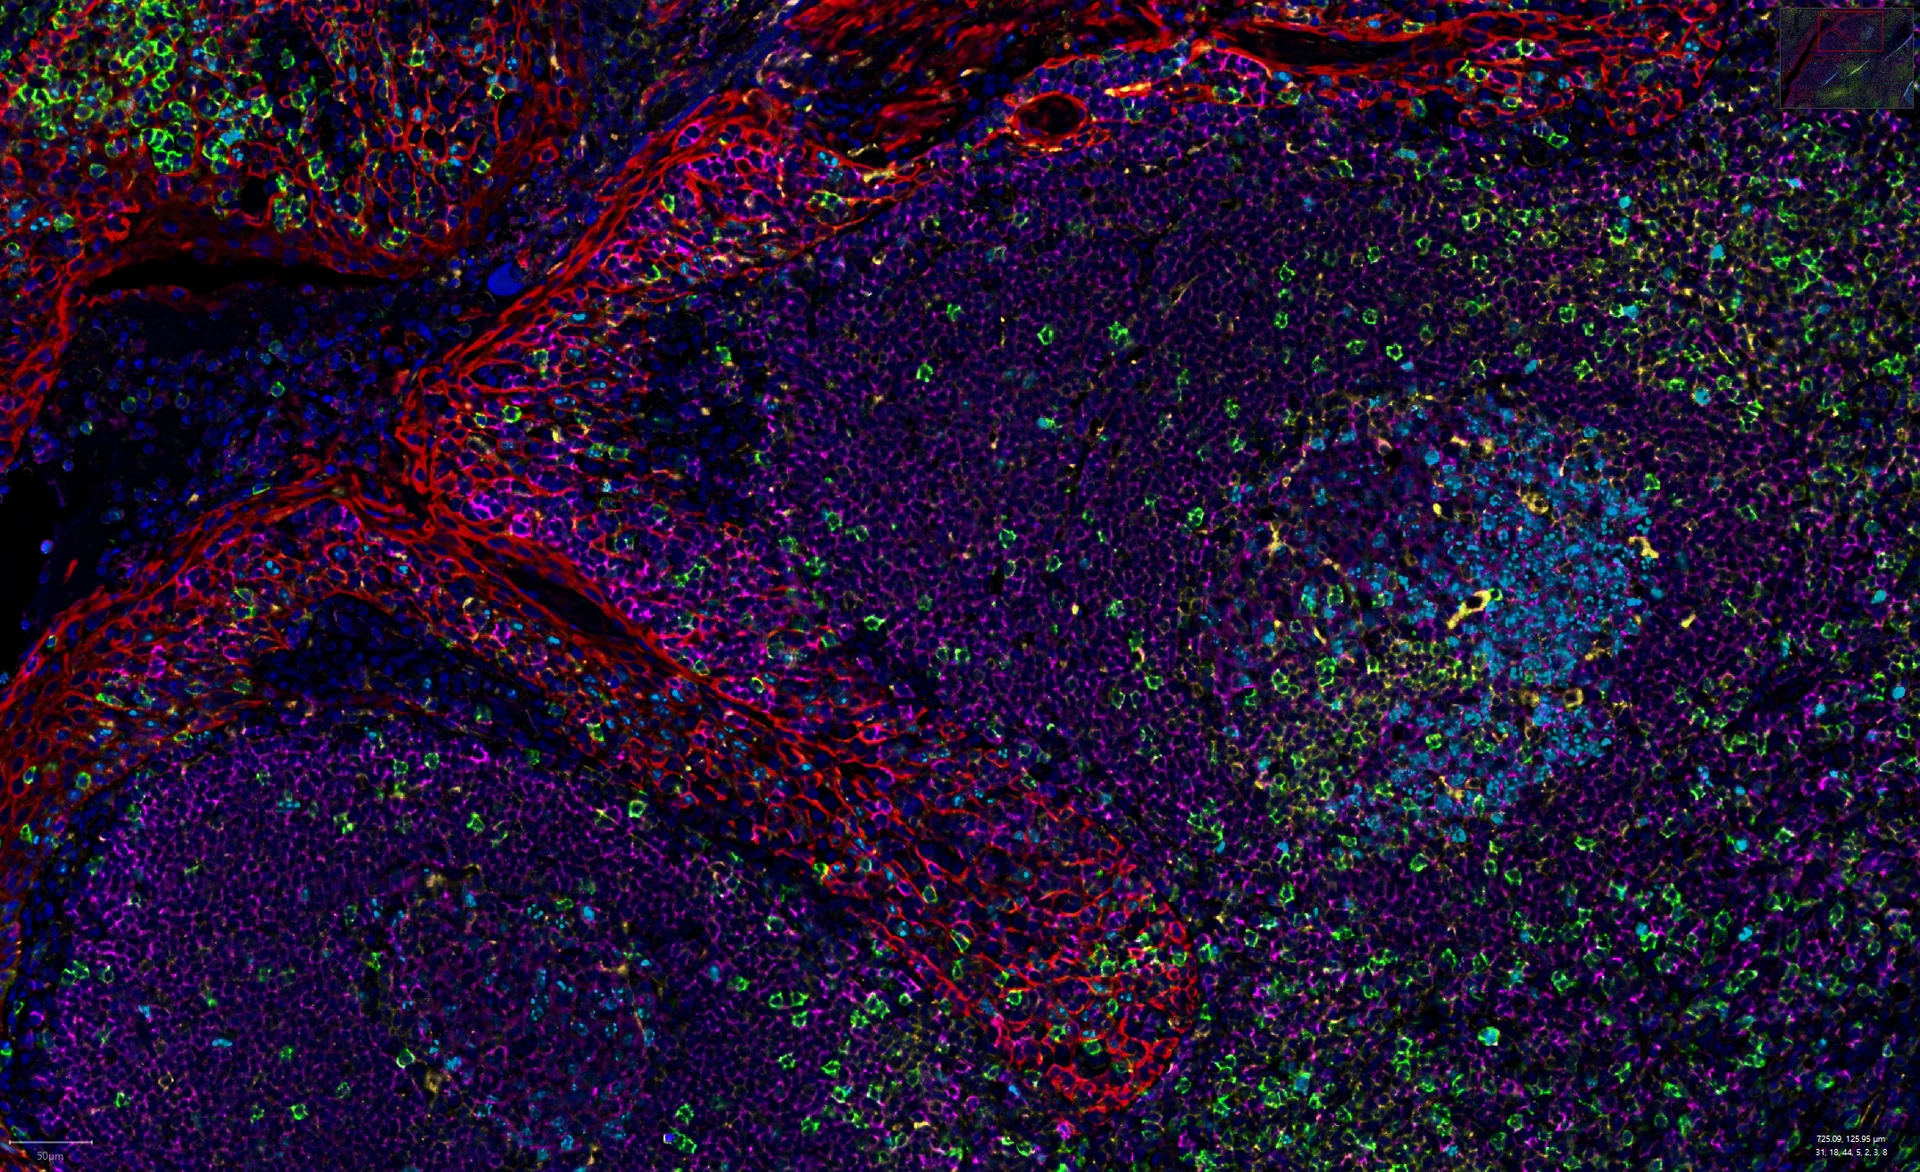

Rodriguez-Calvo_insulitis

Images of islets of Langerhans from diabetic organ donors

Celebration of the 100 years of the discovery of insulin